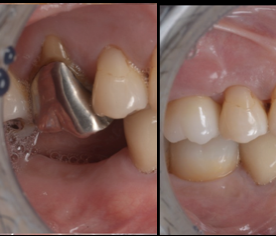

池袋でインナーブリーチ|前歯の神経を失った歯の...